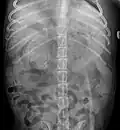

Röntgenaufnahme einer Calcinosis cutis im Rückenbereich eines Hundes -

Röntgenaufnahme eines Karzinoms der rechten Nebenniere (links im Bild) eines Hundes, das durch Kalkablagerung auf Höhe der letzten Rippe erkennbar ist. -